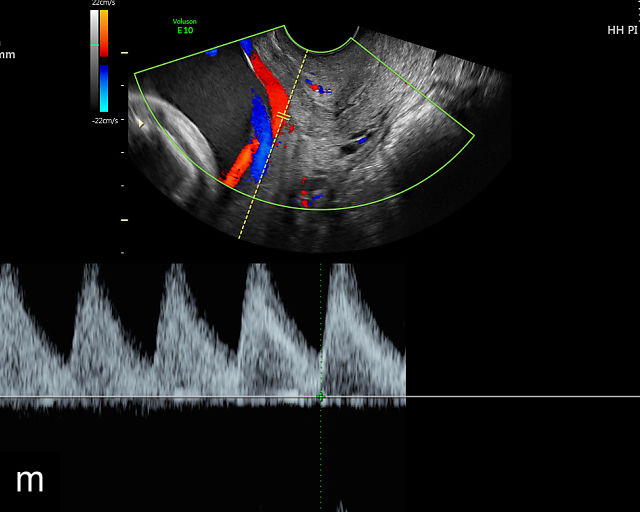

Vasa previa

Vasa previa refers to unprotected fetal vessels running through the membranes over the cervix.30,50,252,253 These vessels often rupture when the membranes rupture during labor or in late pregnancy, resulting in fetal hemorrhage and often exsanguination.252 As a result, this condition is associated with high perinatal mortality.35,252 A large study found a 56% perinatal mortality when vasa previa was not diagnosed prenatally.35 Prenatal diagnosis with ultrasound and cesarean delivery before labor or rupture of the membranes prevents this high perinatal mortality.254,255,256 Risk factors for vasa previa include second-trimester placenta previa or low-lying placenta, velamentous cord insertion, pregnancy resulting from in-vitro fertilization, multifetal gestation and placenta with accessory lobe.30,36,50,257,258,259,260,261

There are three types of vasa previa.30,262 In Type 1, the cord inserts into the membranes rather than the placenta. Unprotected vessels then traverse the membranes over the cervix to insert into the placenta (Figure 21a; Video 12). In Type 2, unprotected vessels running through the membranes over the cervix connect the main placental lobe with an accessory lobe (Figure 21b).263 In Type 3, there is generally a normal placental cord insertion, and unprotected vessels exit one placental edge, run through the membranes over the cervix and then boomerang to insert into the placental edge at another site (Figure 21c).25,28,29,264 Regardless of the type, all these expose the fetus to the same risks.

21